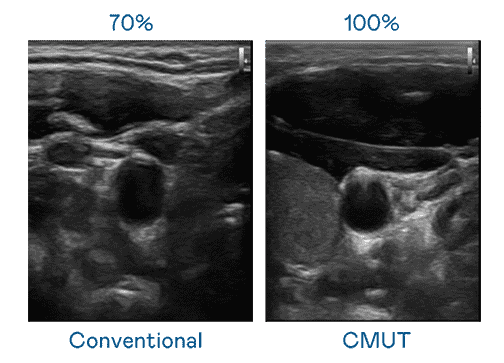

CMUT 技术是一种用电容式微机电元件来产生超音波讯号的技术。。。与传统 PZT 压电式技术相比,,,,CMUT 频宽增加 30%,,,更宽频的超音波讯号让影像解析度大幅提升,,,,是实现高影像品质医疗超音波扫描、、促进精准医疗发展的关键技术。。。

大频宽带来超清晰影像

超音波影像的解析度高低,,,首先取决于探头能发出的讯号频宽。。。z6mg·人生就是博 CMUT 可提供高清晰的超音波讯号,,提供高频宽、、高灵敏度、、、影像纹理细节更高的超音波影像,,,,协助医护人员缩短影像判读时间及利用精准的医疗影像进行诊断。。